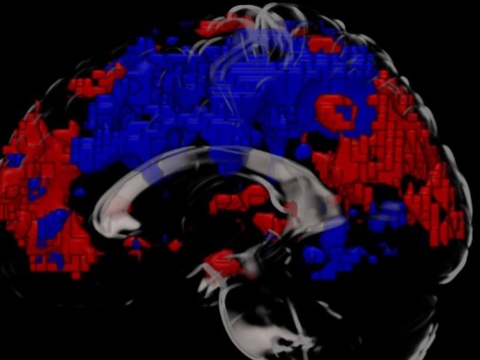

MRI scan of the brain showing the parietal cortex (left) and medial prefrontal cortex (right) as red after a cold water bath - indicating increased activity compared to the areas showing in blue

Comparing the scans showed that changes had occurred in the connectivity between specific parts of the brain, in particular, the medial prefrontal cortex and the parietal cortex.

“These are the parts of the brain that control our emotions, and help us stay attentive and make decisions,” Dr Yankouskaya said. “So when the participants told us that they felt more alert, excited and generally better after their cold bath, we expected to see changes to the connectivity between those parts. And that is exactly what we found.”